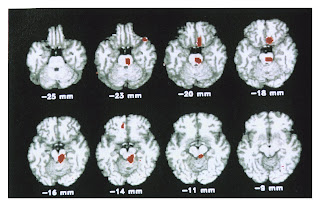

A hemiplegia alternante da infância é uma condiçao muito rara, de causa desconhecida, caracterizada por déficit dimidiado alternante ou mesmo tetraplegia, cujas crises iniciam antes dos 18 meses de idade. Estas manifestaçoes sao episódicas e, freqüentemente, associadas a nistagmo, paralisias oculares transitórias, disfunçao do sistema nervoso autônomo, dispnéia, envolvimento cognitivo, distonia e coreoatetose. A investigaçao laboratorial desta síndrome nao tem evidenciado uma etiologia definida, embora existam possibilidades de uma relaçao com enxaqueca. No presente trabalho, o autor relata um caso e sua resposta ao tratamento com flunarizina. (AU)é uma doença pouco frequente que provoca crises de hemiplegia transitórias, que podem afectar indistintamente um ou outro hemicorpo, inclusivamente ambos simultaneamente. Inicia-se antes dos 18 meses e, em alguns casos, já se apresentam sintomas neo-natais como movimentos oculares anormais, sobretudo nistagmo e crises distónicas ou tónicas. Antes de um ano de idade iniciam-se os ataques hemiplégicos, que desaparecem com o sono. Estes sintomas podem provocar confusão inicial com uma alteração epiléptica. Casos clínicos. A observação de dois doentes masculinos cujas manifestações clínicas apareceram aos 6 meses de idade, como crises tónicas, com desvio do olhar, sem perda da consciência, com uma periodicidade recorrente variável de uma a duas crises por semana ou várias ao dia. Trataram-se inicialmente com fármacos antiepilépticos (FAE), ainda que os exames complementares, entre os quais o electroencefalograma (EEG), tomografía axial computorizada (TAC), ressonância magnética (RM) e exames metabólicos, fossem normais. Conclusões. Uma vez que ainda não se demonstrou um exame específico para a doença, o diagnóstico é fundamentalmente clínico e por exclusão. O tratamento é sintomático com flunarizina. Num dos nossos casos, verificou-se uma diminuição na frequência e intensidade dos ataques hemiplégicos, utilizando a dose única nocturna de 10 mg/dia. A possibilidade de tratar de um doente portador de uma HA com FAE, torna necessário o conhecimento e identificação precoce desta doença, com o fim de melhorar o prognóstico da mesma. Episódios de hemiplegia na infância comprometendo cada lado alternadamente. Associa-se com outros fenômenos paroxísticos e deficiência mental.